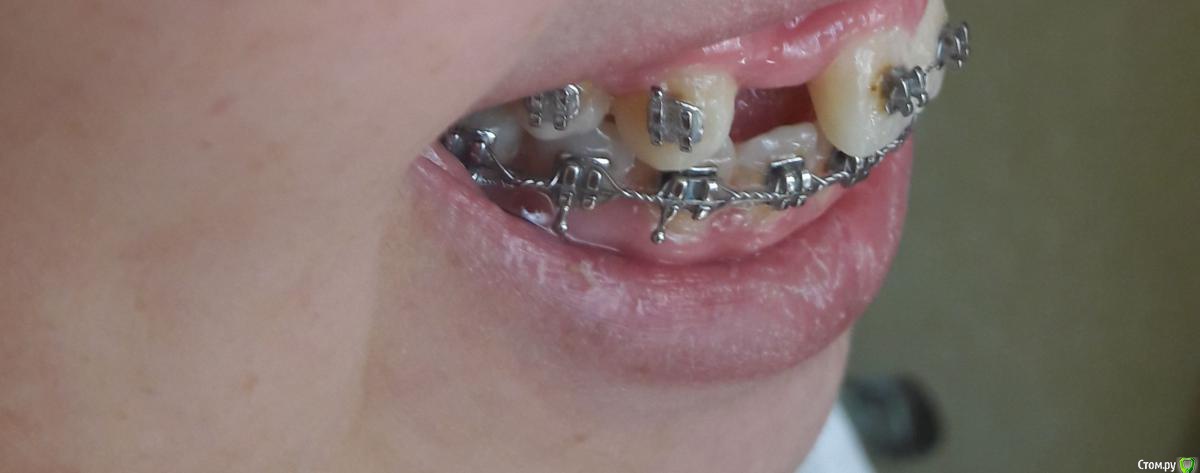

Амина Опубликовано 4 июня, 2016 Автор Поделиться Опубликовано 4 июня, 2016 вот снимок 2016 года Ссылка на комментарий

Амина Опубликовано 4 июня, 2016 Автор Поделиться Опубликовано 4 июня, 2016 Это снимок 2015 года Ссылка на комментарий